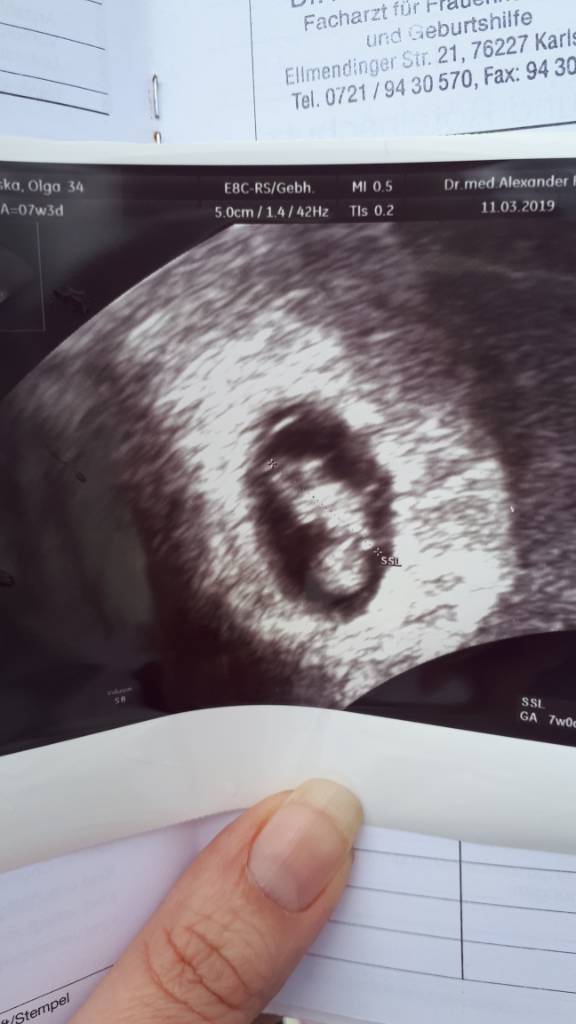

Cześć Ciotki. Przedstawiam wam 9.8 mm bąbelka z bijacym serduszkiem. Matka trochę spokojniejsza. Ufff...

20190311_145152.jpeg